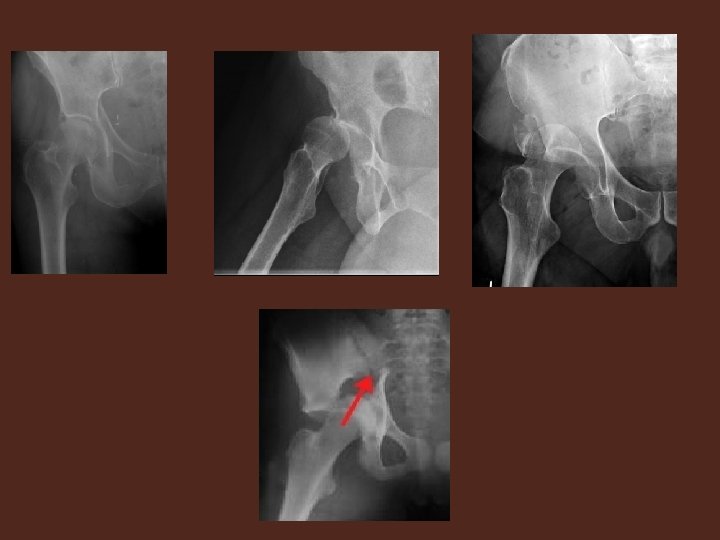

RADIOLOGIE : • fait le diagnostic. • A la base de la classification de JUDET LETOURNEL Le bilan comprend systématiquement I. LA RADIOGRAPHIE: • Bassin de face • Hanche malade de face • 3/4 alaire, 3/4 obturateur===clichés obliques à 45°

II. LE SCANNER: Indispensable si • Polytraumatisé , inconscient • Fracture visible sur radiographie • Forte suspicion clinique+radiographie négative